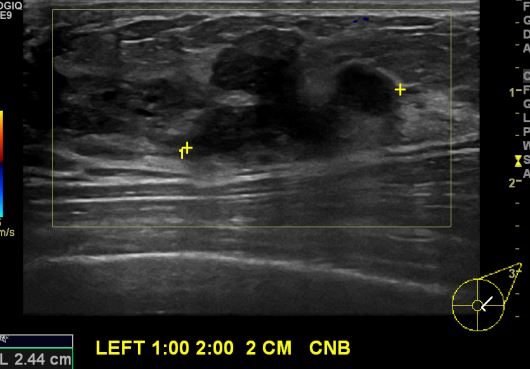

상기환자   좌측유방의 통증으로  내원하신 40대 여성분으로  본원 초음파상

좌측 1시에서 2시 방향에서 2cm 떨어진 거리의 멍울 조직검사 시행하여 좌측 유관암

진단 되었습니다.